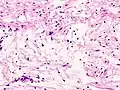

Schwannome mélanotique

C'est une tumeur rare. Elle s'intègre, dans 50 % des cas, dans le complexe de Carney (myxomes cardiaques, pigmentation lentigineuse faciale, anomalies endocriniennes). Il existe au sein de la prolifération d’abondantes mottes de mélanine ainsi que des psammomes (en). Les cellules tumorales expriment la PS100 et l’HMB45 (marqueur de différenciation mélanocytaire).